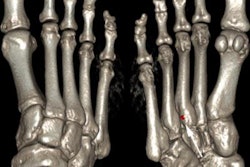

Elderly patient with established and treated rheumatoid arthritis. The patient complained of increased pain and stiffness. Ultrasound shows active synovitis and erosions in multiple metacarpo-phalangeal joints (a = grayscale image, b = power Doppler image). Ultrasound is a useful tool to assess for the presence and to an extent severity of (subclinical) inflammation. Clinical examination can be surprisingly insensitive even in florid inflammation, as shown here. Images courtesy of Dr. Bernhard Tins.Imaging in rheumatology was in the past largely confined to radiographs of the hands and sacroiliac joints helping to establish the diagnosis and then monitoring disease progression. Because radiographs are not very sensitive for early inflammation in inflammatory rheumatic disorders, the demand on imaging services was therefore limited, Tins and Butler explained. Over the last 10-15 years, new drugs and new technologies have brought fresh challenges and opportunities to rheumatology and radiology. New drug treatments allow more effective treatment, preventing many complications, and early diagnosis and disease monitoring have become the major challenges.